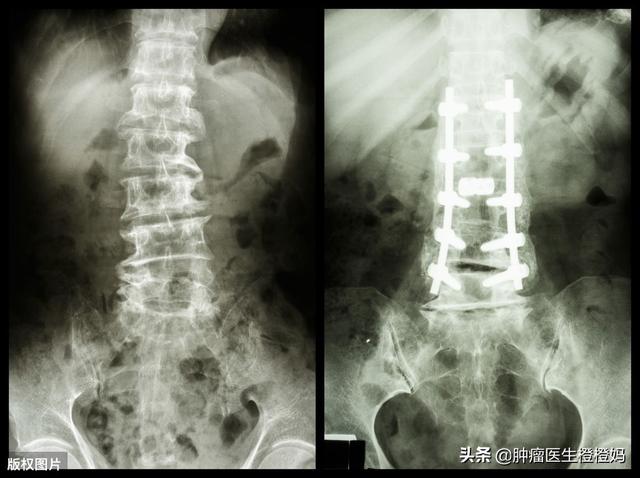

- En cas de fracture, il est temps d'obtenir l'aide d'un chirurgien orthopédique et, selon la situation, il peut être nécessaire de procéder à une fixation fémorale, à un remplissage de ciment vertébral, etc. EtIl est important d'éviter tout mouvement au niveau du site de la fracture afin de ne pas aggraver la blessure.

2) Examen d'imagerie : la radiographie permet de détecter une destruction osseuse précoce et la tumeur peut produire une masse de tissu mou après avoir percé la corticale osseuse ; en plus de la radiographie, un examen par tomodensitométrie, par résonance magnétique ou par PET-CT doit être effectué si nécessaire ;